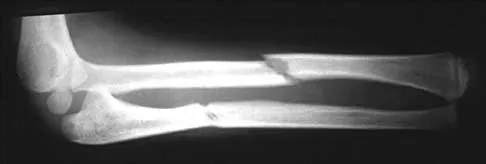

A 15-year-old girl who competes in gymnastics has immediate pain and giving way of the left elbow after falling from the uneven parallel bars and landing on her outstretched arms. Examination reveals swelling and tenderness about the elbow, especially over the medial side. Measurement of elbow motion shows 0 degrees to 125 degrees of flexion, and valgus stress at the elbow is painful. AP, lateral, and stress radiographs are shown in Figures 9a through 9c. Management should consist of

Explanation

Figure 31 shows the radiograph of an 8-year-old boy who has a swollen forearm after falling out of a tree. Examination reveals that all three nerves are functionally intact, and there is no evidence of circulatory embarrassment. Management should consist of

Explanation

Question 92

A healthy, active, independent 74-year-old woman fell and sustained the elbow injury shown in Figures 41a and 41b. Management should consist of